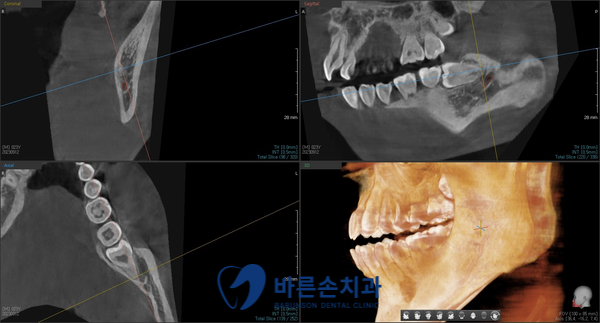

사랑니 발치에 앞서

3D CT 촬영을 하였습니다

Before 23.06.28

사랑니의 형태와 위치, 아래턱뼈에 있는 하치조신경관의 해부학적 위치를

정확히 확인 후 발치에 들어갑니다.